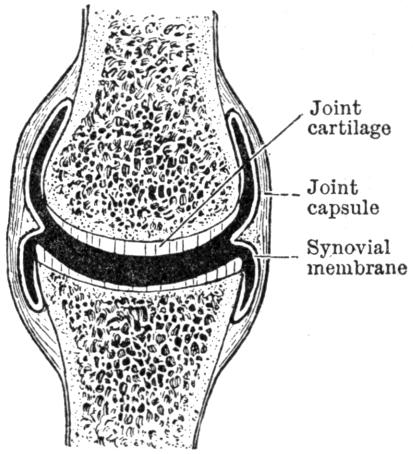

| III. | The Skeleton | H 28 |